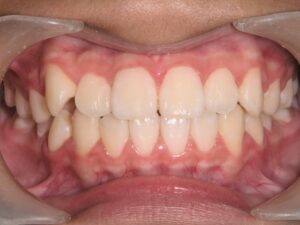

第2期治療終了時

顔貌写真

口腔内写真

治療結果

上下の歯のデコボコが改善

全体的な咬み合わせの緊密化

治療費(調整料含めて)

約95万円(第1期治療…40万円、第2期治療…55万円)

第1期治療期間

第1期治療開始:2021年8月

第1期治療終了:2022年1月

動的治療期間:5か月

第2期治療期間

第2期治療開始:2024年9月

第2期治療終了:2025年7月

動的治療期間:10か月

合計期間

3年10か月(動的治療期間:1年3か月+経過観察期間:2年7か月)

患者様は歯のデコボコを主訴で来院しましたが、第1期治療で歯列拡大+前歯部矯正を行ったことで、第2期治療で非抜歯矯正にて治療終了することができました。